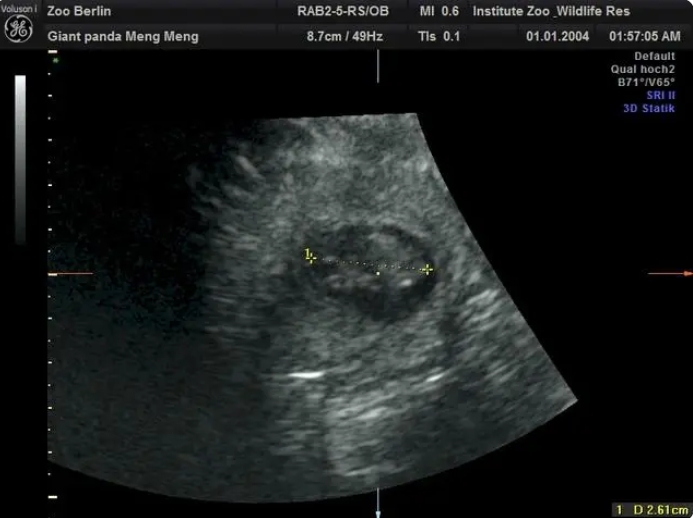

德國柏林動物園當地時間13日宣布,11歲的旅德大熊貓「夢夢」再次懷上雙胞胎。

在園方11日上午進行的超聲檢查中,工作人員清楚地檢測到兩個熊貓?zhí)旱男奶D壳皟蓚€胎兒身長約2.5厘米。

柏林動物園介紹,根據目前胚胎的大小,如果一切順利的話,大熊貓雙胞胎預計將於8月底出生。